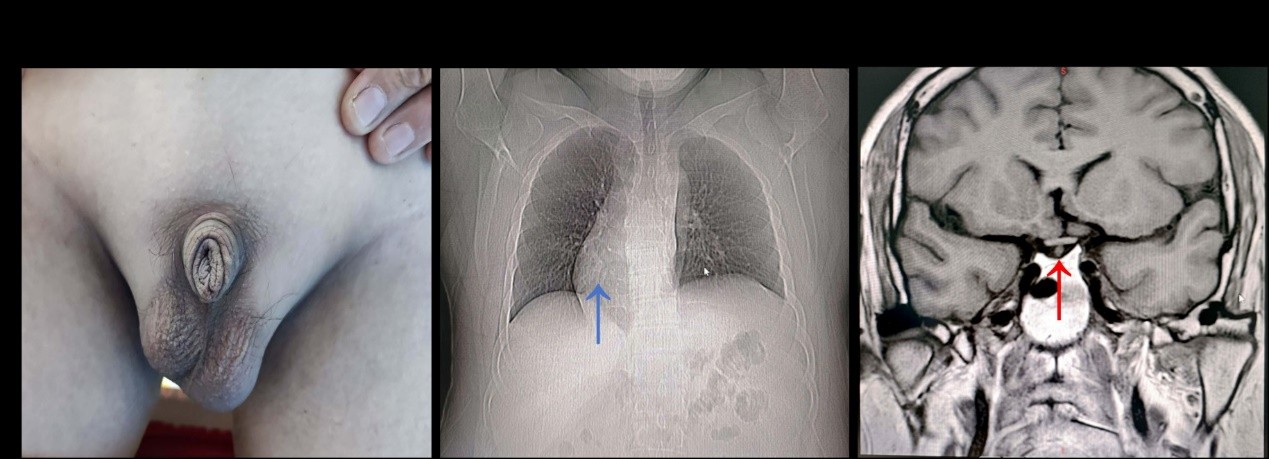

病例摘要及病例特点 37岁中年男性,因双下肢浮肿1年,加重1周就诊。 现病史:患者自诉于1年前开始间断出现双下肢浮肿,以脚踝部水肿为主,伴泡沫尿,水肿可自行缓解,未予重视及进一步诊治。近1周,患者出现双下肢浮肿加重,水肿蔓延至胫前,无尿量减少、皮疹、关节痛、脱发、腹痛、血便、听力下降、口干、眼干等不适,于我院门诊查尿蛋白4+,血肌酐181umol/l,门诊以肾病综合征,肾功能不全收治入院。自起病以来,精神、食欲、睡眠正常,大便正常,小便如上述,体重无变化。 既往史:从小嗅觉丧失,14岁时发现双侧睾丸发育不良,32岁时在我院确诊为卡尔曼综合征,当时查肌酐正常,间断使用雄性激素治疗2月后停用。否认高血压、冠心病及糖尿病病史。否认乙肝、丙肝等传染病史。否认外伤、手术史,否认药物、食物过敏史。 个人史信息:职员。否认疫区、疫水接触史。否认吸烟、饮酒史。 婚育史信息:未婚未育。 家族史信息:父母均体健,有一个姐姐已婚育1子。父母及姐姐无明确高血压、糖尿病、肾脏病或自身免疫性疾病史。 入院查体:身高188cm,体重114.7Kg,BMI 32.18kg/m2,血压131/83mmHg。眼睑浮肿,双下肢II水肿,双侧乳房发育,心界右偏,肺、腹、神经系统查体均阴性。生殖器查体:阴毛稀疏,外阴短小,约5cm,双侧睾丸缩小(图1A)。 诊治经过:入院后完善相关检验检查:查肌酐181umol/L、血尿素氮8.57mmol/L,血白蛋白27.8g/L,尿蛋白(4+),尿微量白蛋白/尿肌酐 14316mg/g.Cr,24小时尿蛋白定量19g/24h,尿红细胞183/HPF,尿白细胞45/HPF;总胆固醇9.38mmol/l,甘油三酯 9.25mmol/l,血常规、凝血六项、电解质、空腹血糖、甲功、抗核抗体谱、抗中性粒细胞胞浆抗体、抗GBM抗体、抗类风湿因子、补体、血固定电泳、肝炎、艾滋病毒等检查均正常。相关激素检查:睾酮 0.32ng/ml,黄体生成素 0.29mIU/ml,均明显降低,余雌激素、促肾上腺皮质激素、生长激素、泌乳素、卵泡生成素等均正常。 十二通道心电图提示:窦性心律,正常心电图;64排胸部CT提示:纵膈右移(图1B),右肺上叶可见多发实性结节,考虑增殖灶;心脏超声示:心脏位于中纵隔,大部分位于中线右侧,心脏各腔室大小正常,EF:62%;结论:镜面右位心,左室舒张功能降低;腹部彩超提示:脂肪肝,左肾区域未见明显正常肾脏样回声显示。右肾长13.8cm、厚7.8cm,形态正常,包膜光滑,皮质回声均质,集合系统未见分离。右侧输尿管上段管腔未见扩张,可见段未见异常回声显示。膀胱充盈欠佳,可见部分内部未见明确结石及其它占位性回声。生殖器超声示:左侧睾丸约1.5×0.7cm,右侧睾丸约1.6×0.6cm,双侧睾丸在位,形态缩小,双侧对比无差别。双侧附睾形态大小正常,双侧对比无明显差别;CDFI示血流信号未显示异常增减;双侧睾丸、附睾区域未见其他确切异常占位性回声显示;结论:双侧睾丸缩小。垂体磁共振检查示:脑垂体形态大小正常,高度约0.6cm,其内未见明确异常信号。垂体柄右偏曲,视交叉无明显受压,海绵窦区未见异常征象。所见大脑各叶形态、大小、信号未见异常。结论:脑垂体大小及形态均正常,垂体柄右偏(图1C)。 图1:患者临床表现 A:阴茎及睾丸较小;B:右位心(蓝色箭头);C:垂体柄轻度右偏(红色箭头)。 入院第2天患者排除肾穿刺绝对禁忌症后完善肾活检(图2)。光镜描述:2条皮髓组织,10个完整肾小球,见3个球性硬化,1个节段硬化。部分肾小球体积增大,细胞数90-110个/球,系膜细胞及系膜基质轻度增生,足细胞肿胀脱落,肾小球内可见炎细胞浸润(0-3个/球),毛细血管袢饱满僵硬,袢内血浆成分沉积,开放欠佳。3个肾小球Bowman’s囊壁增厚、分层,1处球囊粘连。PASM及Masson染色下肾小球基底膜增厚,上皮下可见嗜复红物沉积,可见钉突,未见双轨形成。肾间质可见少量泡沫细胞,肾小管上皮细胞水肿,颗粒样变性及空泡样变性,管腔内可见透明管型。多灶性肾小管萎缩、间质纤维化及单个核细胞浸润。部分肾小管囊样扩张。弓动脉、小叶间动脉、小动脉未见明显异常。免疫荧光:见3个肾小球,IgG(+++)、IgG3(+)、IgG4(++)、CLq(+-)、PLA2R(++)沿毛细血管呈颗粒样沉积,Ig G1(-)、IgG2(+-)、IgA(+-)、IgM(+-)、C3(+-)、C4(-)。电镜描述:电镜下见毛细血管内皮细胞明显空泡变性,个别管腔内可见红细胞聚集,无明显内皮细胞增生,毛细血管襻开放。肾小囊壁层无明显增厚,壁层细胞空泡变性,无明显增生。基底膜不规则增厚,厚度达1200nm。脏层上皮细胞肿胀,空泡变性,足突弥漫融合。上皮下、基底膜内见电子致密物沉积,部分电子致密物包裹在基底膜内,有吸收表现。系膜细胞和基质增生,未见电子致密物沉积。肾小管上皮细胞空泡变性。肾间质无特殊病变。病理诊断:结合患者光镜及电镜检查,病理诊断为1.膜性肾病Ⅲ期 2.局灶节段硬化性肾小球肾炎(NOS型);患者完善抗磷脂酶A2受体(PLA2R)抗体检测为188.63RU/ml。最终患者诊断为原发性膜性肾病Ⅲ期、肾病综合征、卡尔曼综合征、慢性肾脏病3期、左肾缺如。 图2: 肾活检病理结果 A:PAS染色显示肾小球基底膜增厚。B:PASM 染色显示肾小球节段硬化。C:免疫荧光染色显示肾小球毛细血管沿线颗粒状IgG沉积。比例尺= 20μm 。D:电子显微镜显示基底膜不规则增厚,厚度达1200nm。足细胞肿胀、足突弥漫性融合、上皮下及基底膜中电子致密物质沉积。比例尺= 2μm 。 患者进一步完善完善了基因检测,结果回示: 表1:基因突变检测结果 基因 转录本 染色体位置 参考碱基 变异碱基 变异位点 氨基酸变化 突变类型 变异状态 变异丰度 AMER1 ENST00000330258 X:63409958 C T c.3209G>A p.Ser1070Asn 错义突变 纯合子 100% 治疗及随访: 患者膜性肾病合并大量蛋白尿,为高危组,经沟通后患者最终选择激素+他克莫司治疗,并同时予以厄贝沙坦降尿蛋白、百令片护肾、护胃、补钙等综合治疗,为期12周的临床随访显示多项实验室参数有所改善。肌酐水平从181 μmol/L降至122 μmol/L,24小时尿蛋白定量从19克降至3.5克(表1)。FK-506谷浓度维持在治疗范围内。 表2:入院及随访结果 0 周 4 周 8 周 12 周 参考范围 肌酐 (umol/l) 181 162 136 122 57.0-97.0 尿素(mmol/L) 8.81 8.21 8.01 9.45 3.1-8 血清白蛋白(g/L) 27.8 31.6 29.6 32 40.0-55.0 总胆固醇(mmol/L) 9.38 8.89 9.78 10.2 0-5.2 甘油三酯(mmol/L) 9.25 7.3 6.5 6.44 0.0-1.7 他克莫司浓度(ng/ml) 7.3 4.1 5.6 1.75-7.81 尿蛋白 4+ 4+ 4+ 3+ Negative 尿红细胞/ 高倍镜 183 230 50 14 0-10 尿白细胞细胞/ 高倍镜 45 30 10 2 0-10 尿微量白蛋白/尿肌酐(mg/g.Cr) 14316 7776 7659 5218 0.0-30.0 24小时尿蛋白定量(g/24h) 19 12 3.5 0.0-0.1 讨论 卡尔曼综合征(KS)是一组罕见疾病,其特征为促性腺激素释放激素的产生和/或作用缺陷,并伴有嗅觉缺失或嗅觉减退。该综合征可能与多种先天性异常相关,包括唇腭裂、单侧肾缺如、单侧或双侧隐睾症、双手共动症(或镜像运动)、并指(或趾畸形)或其他骨骼异常等[1]。该病在临床和遗传学上具有异质性,超过40个基因参与其发病机制,包括KAL1、FGFR1和SEMA3A28,可呈常染色体显性遗传、常染色体隐性遗传或X连锁隐性遗传,目前仅30-40%的KS患者明确其基因突变的序列[2]。正因为如此,KS的诊断需依靠临床表现及辅助检查,目前主要的临床诊断依据包括:(1)性腺低下:患者可表现为第二性征发育不明显,查体可见体毛稀疏,小阴茎、小睾丸,阴囊彩超提示睾丸体积偏小。(2)嗅觉异常:可表现为双鼻或单侧的嗅觉减退或缺失。(3)实验室检测提示性激素下降,促性腺激素下降,但垂体的其他激素正常。(4)部分可伴有其他系统的缺陷,包括唇/腭裂、单侧肾缺如、单侧或双侧隐睾、双手联带运动(或镜像运动)、并指(趾)畸形等其他系统的异常[3-4]。 该患者自小发现双侧嗅觉丧失,14岁时比同龄人发育缓慢且无第二性征未发育。诉18岁以后身高增长快,22岁时停止,目前身高188cm,体重114.7Kg,BMI 32.18kg/m2,体型偏肥胖;5年前在我院查小阴茎、小睾丸,雄激素及黄体生成素下低,临床诊断为KS。此次住院后查腹部超声提示左侧肾脏缺如,心脏呈镜面右位心,生殖器超声提示双侧睾丸缩小,综上患者诊断KS明确。 目前已知的KS患者肾脏的表现主要为单侧肾脏缺如,已有一些病例报告描述了KS患者出现蛋白尿及肾功能的异常。一篇病例报告描述了一名患有X连锁KS的10岁儿童出现了肾病综合征,但该患者同时患有X连锁鱼鳞病综合征,这是一种由类固醇硫酸酯酶缺乏引起的遗传性皮肤病。胆固醇硫酸酯的积累可能干扰肾小球滤过膜的正常功能导致蛋白尿。因此,该患者的蛋白尿可能与鱼鳞病综合征有关[5]。另一项针对7例伴有单侧肾脏的KS患者的回顾性分析发现,有2例患者表现为肾病综合征,且蛋白尿可出现在高血压和肾功能损害之前。推测可能是由于单侧肾脏导致的局灶节段硬化性肾小球肾炎引起,但这2例患者均未得到明确诊断,也无肾活检报告[6]。在我们的病例中,肾活检证实了PMN,患者被诊断为原发性膜性肾病。这是首例报道的KS合并PMN的病例。同时也看到患者有局灶节段硬化性肾小球肾炎NOS型,这一部分也符合既往既往文献的推测。 为进一步论证患者KS基因突变类型及肾病综合征的是否同基因突变相关,患者进行了基因检测,结果显示AMER1基因存在错义突变,突变丰度为100%(表1),其父母和姐姐均未发现类似突变。该突变可能是KS的一种新突变。因为一项大样本系列研究探讨了KS特定的基因型-表型的关系表明,单侧肾缺如和联带运动(镜像运动)似乎是X连锁型KS的表型标记物[7]。而AMER1基因位正好位于X染色体上,是WNT/β-catenin通路的负调控因子,在胚胎发育中起重要作用,并在包括神经系统、鼻上皮、性腺和肾脏等多种组织中表达,同KS靶器官一致[8-10]。尽管在患者的父母和姐姐中未发现类似突变,但患者临床特征的支持,包括右位心和左肾缺如,这些都是X连锁型KS的表型标记物,表明AMER1的X连锁突变可能与KS有关。 同时,在全外显子组测序中未发现与肾病综合征相关的基因突变,表明患者的膜性肾病可能是一种偶然现象,而非KS的并发症。但这同样引发了对共享的遗传或免疫失调机制的推测。免疫抑制治疗在实现肾病部分缓解方面的有效性,支持了在此背景下PMN的免疫介导性质。 本病例拓宽了KS的表型谱,并对神经发育基因缺陷与免疫介导的肾损伤之间的相互作用提出了关键问题。它强调了多学科评估在罕见遗传综合征中的重要性,并为未来研究神经内分泌与肾脏疾病之间的共同分子通路提供了基础。需要进一步的研究来阐明KS与PMN之间的关系,并探索AMER1等基因在这些疾病中的作用。 参考文献 1. Kumar Yadav R, Qi B, Wen J, Gang X, Banerjee S. Kallmann syndrome: Diagnostics and management. Clin Chim Acta. 2025 Jan 15;565:119994. 2. Chu G, Li P, Zhao Q, He R, Zhao Y. Mutation spectrum of Kallmann syndrome: identification of five novel mutations across ANOS1 and FGFR1. Reprod Biol Endocrinol. 2023 Mar 1;21(1):23. 3. Sonne J, Lopez-Ojeda W. Kallmann Syndrome. 2023 May 16. In: StatPearls [Internet]. Treasure Island (FL): StatPearls Publishing; 2024 Jan–. 4. Dwyer AA, Stamou MI, Anghel E, et al. Reproductive Phenotypes and Genotypes in Men With IHH. J Clin Endocrinol Metab. 2023 Mar 10;108(4):897-908. 5. Krishnamurthy S, Kapoor S, Yadav S. Nephrotic syndrome with X-linked ichthyosis, Kallmann Syndrome and unilateral renal agenesis. Indian Pediatr. 2007 Apr;44(4):301-3. 6. Duke V, Quinton R, Gordon I, Bouloux PM, Woolf AS. Proteinuria, hypertension and chronic renal failure in X-linked Kallmanns syndrome, a defined genetic cause of solitary functioning kidney. Nephrol Dial Transplant. 1998 Aug;13(8):1998-2003. 7. Stamou MI, Georgopoulos NA. Kallmann syndrome: phenotype and genotype of hypogonadotropic hypogonadism. Metabolism. 2018 Sep;86:124-34. 8. Huff V. Wilms tumours: about tumour suppressor genes, an oncogene and a chameleon gene. Nat Rev Cancer. 2011 Feb;11(2):111-21. 9. Mi J, Parthasarathy P, Halliday BJ, Morgan T, Dean J, Nowaczyk MJM, et al. Deletion of Exon 1 in AMER1 in Osteopathia Striata with Cranial Sclerosis. Genes (Basel). 2020 Nov 30;11(12). 10. Lei S, Chen C, Han F, Deng J, Huang D, Qian L, et al. AMER1 deficiency promotes the distant metastasis of colorectal cancer by inhibiting SLC7A11- and FTL-mediated ferroptosis. Cell Rep. 2023 Sep 26;42(9):113110.